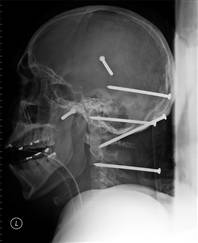

| Recent Headline: Man recovering after nails driven into skull.

LOS ANGELES - A construction worker had six nails driven into his head in an accident with a high-powered nail gun, but doctors said Wednesday they expect him to make a full recovery. |

| My Comment: Ok, ok, one nail is an accident, maybe two. Six is attempted murder. This guy must owe money to someone named Don Vito. The man does not remember getting hit with the high powered nail gun, so all the reports as to what happened came from the co-worker who blasted this guy's noggin. Of course the co-worker will say it is an accident but I am sure he was trying to kill him. Lets call the reporter who wrote the story and the police investigator just plain stupid for believing that the six giant nails in the brain was just an "ACCIDENT". Yeah Right! |